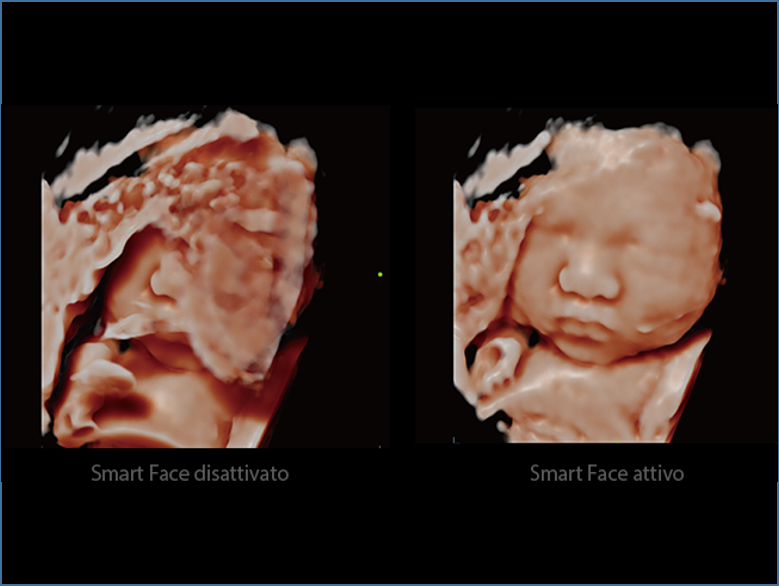

DC-80A con X-Insight mette a disposizione strumenti di una intelligenza eccezionale specifici per la cura della donna, dalla fertilit├Ā allo screening prenatale, e al post partum.

Un'esperienza esaltante che permette di concentrarsi sulla cura del paziente con esami di alta qualit├Ā e facili da eseguire. La tecnologia X-Insight consente eccezionale usabilit├Ā, facilit├Ā nell'esecuzione dell'esame, gestione flessibile, tutto oltre le aspettative.

Immagini cliniche